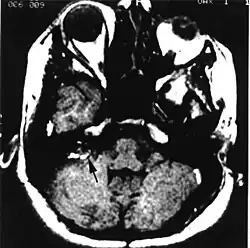

Ośrodkowy układ nerwowy

U wielu pacjentów pierwszym objawem choroby jest wystąpienie zmian narządowych w ośrodkowym układzie nerwowym o charakterze naczyniaków zarodkowych. Najczęstsze (75%)[3] są w móżdżku (haemangioblastoma cerebelli); poza móżdżkiem, guzy tego typu lokalizują się także w rdzeniu przedłużonym (haemangioblastoma medullae oblongatae) i rdzeniu kręgowym (haemangioblastoma medullae spinalis). Objawy wywoływane przez guza zależą od jego lokalizacji i rozmiarów. Guzy móżdżku początkowo nie dają objawów; potem pojawiają się bóle i zawroty głowy, nudności i wymioty, objawy móżdżkowe, dysmetria i porażenie nerwu IX. Naczyniak zarodkowy rdzenia przedłużonego objawia się z reguły bólami głowy, nudnościami, wymiotami, upośledzeniem czucia i motoryki, zaburzeniami połykania, oddychania. Naczyniaki zarodkowe rdzenia kręgowego dają bardzo niespecyficzny zestaw objawów obejmujący bóle, niedowłady, zaniki mięśniowe, zaburzenia czucia głębokiego i/lub powierzchniowego. W obrębie rdzenia przedłużonego i rdzenia kręgowego może rozwinąć się jamistość rdzenia (syringomyelia).